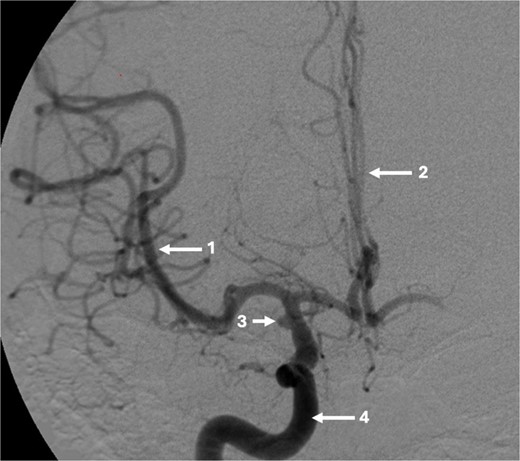

A 43-year-old lady, with known hypertension, presented with severe and sudden onset headache in 2010. Initial computed tomography (CT) head confirmed a diffuse subarachnoid haemorrhage (images not available) and a subsequent CT angiogram showed a right supraclinoid internal carotid artery (ICA) aneurysm (Fig. 1). CT Angiogram also showed an unruptured left posterior communicating which was thought not to be related to this patient’s presentation and managed conservatively with serial imaging. The patient underwent emergency craniotomy on the same day where an encircling Sundt clip was applied to secure the aneurysm. She made a full neurological recovery and was discharged from hospital. Post-operative day 1 CT angiogram demonstrated relatively normal calibre of the right A1 portion of anterior cerebral artery (ACA) and M1 portion of middle cerebral artery (MCA), in the terminal carotid region (Fig. 2).

Axial post-operative CT angiogram demonstrating the (1) encircling clip occlusion of the terminal internal carotid artery aneurysm with a relatively normal calibre of (2) A1 and, (3) M1.